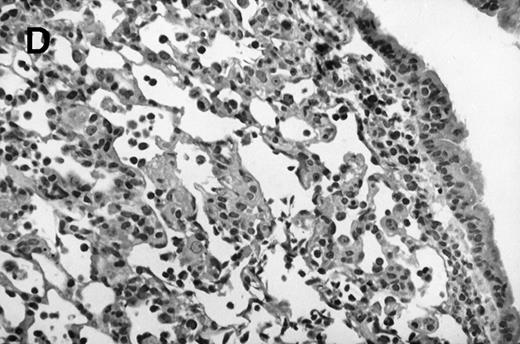

Allogeneic transplanted mice (B10.BR → CBA) with GVHD and, as controls, allogeneic transplanted mice without GVHD and syngeneic transplanted mice (B10.BR → B10.BR) were infected intranasally with HSV-1 at 12 weeks after transplantation. As an additional control, age-matched normal CBA mice were infected as well. Histological examination of lungs was performed in mock-infected mice and in mice at day 7 after infection. Allogeneic transplant recipients with GVHD showed increased pathology (Fig 1). Scores reflecting the periluminal histopathologic changes were significantly higher (P = .05; Student's t-test) in allogeneic transplant recipients with GVHD, when compared with control mice (Fig 2). The periluminal histopathologic scores were also higher in allogeneic transplant recipients with GVHD, when compared with normal CBA mice, at days 4, 10, and 14 after infection (data not shown). No significant differences were observed in the scores reflecting the parenchymal histopathologic changes (data not shown). Because the results in syngeneic transplanted mice were very similar to those in allogeneic transplanted mice without GVHD, the latter, which are the most appropriate control for procedural effects and for the effect of GVHD, and normal CBA mice, were used as controls in further experiments.

Allogeneic transplant recipients with GVHD showed increased pathology. Photomicrographs of lung sections stained with hematoxylin and eosin show evidence of increased pathology in infected allogeneic GVHD mice. (A) Normal CBA, mock-infected, original magnification × 25; (B) normal CBA, mock-infected, original magnification × 100; (C) normal CBA, infected, original magnification × 40; (D) normal CBA, infected, original magnification × 100; (E) allogeneic GVHD, mock-infected, original magnification × 10; (F) allogeneic GVHD, mock-infected, original magnification × 75; (G) allogeneic GVHD, infected, original magnification × 10; (H) allogeneic GVHD, infected, original magnification × 100.